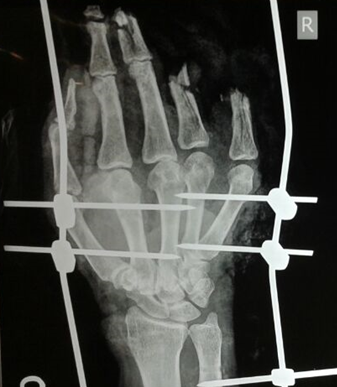

Partial Hand Amputation

Hand Fracture Fixation